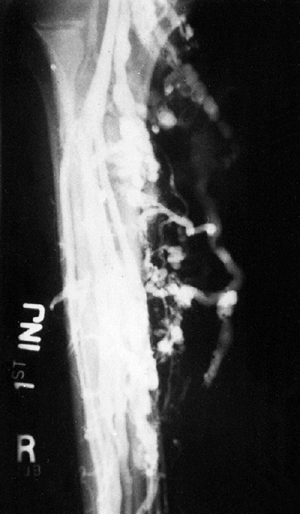

osteosarcoma. The extent of the lesion, especially the intraosseous

component, is more clearly defined by MRI. The lesion can be seen in

all three planes, and its soft tissue extension is easily appreciated.

It is critical that the entire bone be included on at least one plane

(usually the coronal view). The tumor should be viewed with at least a

T1-weighted (with and without gadolinium) image, a T2-weighted image,

and a fat-suppressed image.

![]() |

Figure 14.8

Classic high-grade osteosarcoma of the proximal tibia. The tibia was bisected for examination. The tumor is composed of an osteoblastic component in the metaphysis, which is up to, and just through, the epiphyseal plate; there is also a more distal cystic component. The tumor has penetrated the cortex, and has a small extracortical component. The patient had not received preoperative chemotherapy, but was treated successfully with limb salvage resection and knee arthrodesis. The patient received postoperative adjuvant chemotherapy, and has been continuously free of disease for 4 years. |